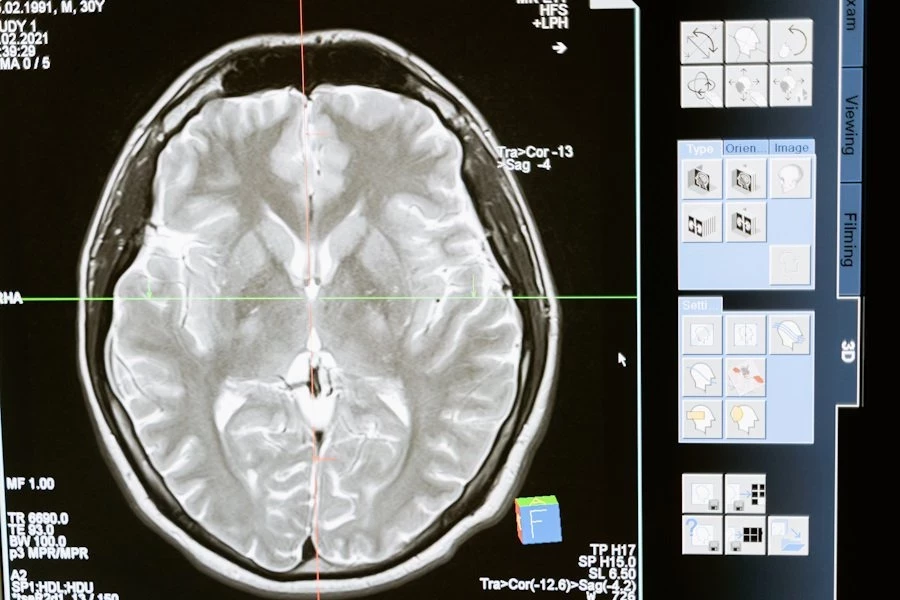

Глиобластома — это злокачественная опухоль, которая часто оказывается устойчивой к лечению. Препятствия на пути к её терапии включают сложность хирургического удаления, низкую эффективность химиотерапии из-за гематоэнцефалического барьера, а также высокий риск рецидивов.